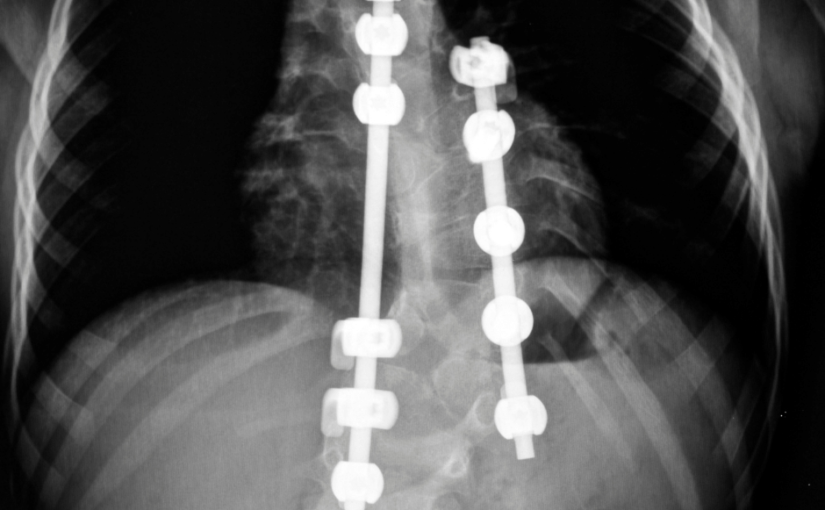

Últimos Avances en Cirugía de Escoliosis

Los investigadores han estado trabajando constantemente en técnicas avanzadas para tratar la escoliosis de manera eficiente y hoy en día existen bastantes tratamientos quirúrgicos que afirman tratar la escoliosis. La mayoría de los procedimientos realizados para la escoliosis esencialmente incluyen el uso de implantes atornillados en su columna vertebral para evitar que su columna se…